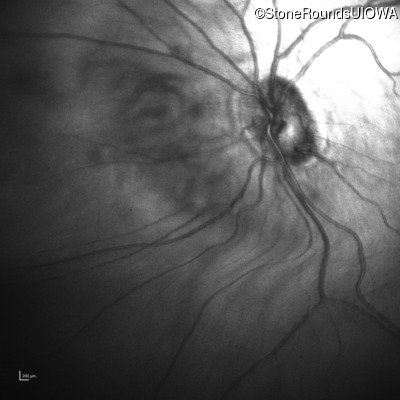

Infrared Fundus Photograph - Right - 20/100

Exemplar